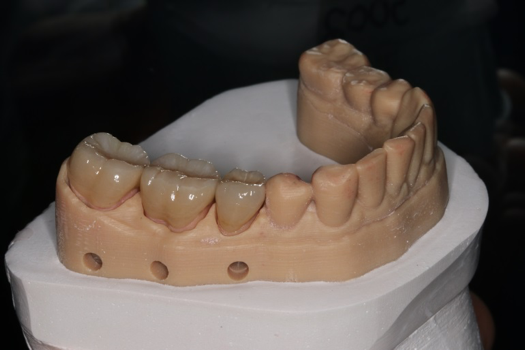

The next case follows the digital protocol for fully guided surgery and prosthetics. A CBCT radiograph, digital impression, and digital photography were the cornerstones to the success of this case. The 3D data set was electronically delivered to the dental laboratory. The data were merged and the process to develop the plan was initiated. The use of CBCT was essential in this case, particularly due to minimal space for placement of individual implants and single-unit crowns. The patient's chief concern was that she wanted to have single-unit crowns instead of fixed crown-and-bridge restorations because she was worried that she would someday find herself in an assisted-living facility; if that were to happen, she wondered, who would help floss under her bridge work? Her decision was to have single implants with individual crowns. CBCT technology is much more accurate in evaluating space maintenance and management.10 Periapicals in the past were rather close for calculating spacing; however, the CBCT identifies the buccal-lingual dimensions as well as the mesial-distal measurements. On review of the completed proposals for implant placement and provisionals, it was determined that there was sufficient spacing for implant placement to allow appropriate emergence profiles for the provisionals and then eventually the final single-unit cemented crowns. The proposal was accepted, and a 3D-printed surgical stent was fabricated, along with the PMMA provisionals (Figure 29 through Figure 35).

On the day of surgery, the plan was to extract teeth Nos. 21, 23, 24, 25, and 26, place 3.0 x 13-mm implants in the anterior region due to limited spacing, and place a 4.1 x 10-mm implant in the No. 21 extraction site. Before the extractions were performed, the No. 23 pontic was sectioned from the existing 2-unit cantilevered bridge utilizing ceramic and metal high speed rotary cutting burs ZR 6881 and H34L (Komet-USA), respectively. After removal of the pontic and extractions, the surgical guide was verified to be seating positively (Figure 36 through Figure 38). Surgical guide protocol was followed, and all implants were successfully placed and torqued to a value of greater than 35 Ncm (Figure 39 and Figure 40). All implants were placed without flapping, with the exception of No. 23. The flap was elevated to reposition lingual keratinized tissue facially for enhanced esthetic tissue profile. The implants were then prepared with a high-speed carbide bur (Komet-USA) with copious amounts of water (Figure 41 and Figure 42). The one-piece 3.0-mm diameter implant served the needs of the patient's spacing requirements. Inter-occlusal space requirements and path of draw were verified. The PMMA provisionals were air abraded and relined with crown-and-bridge material (Figure 43 through Figure 45).

Fig 43. PMMA provisional digitally fabricated and milled.

Figure 43